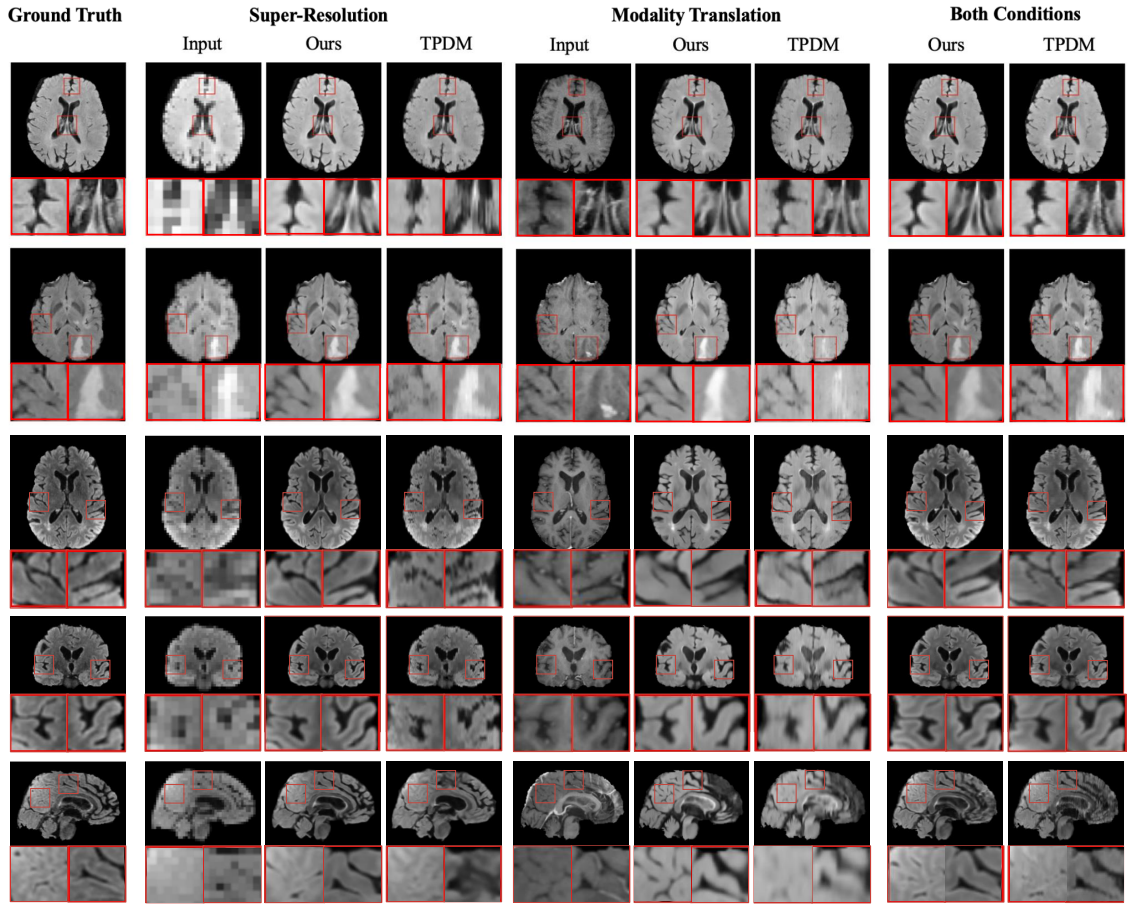

Visual comparison of generated samples for three different conditions. The first three rows show axial view slices

from different MRI volumes. Neither Score-Fusion nor TPDM have a 2D model trained in this direction. The last three rows

show slices for the same MRI volume in all three views. Score-Fusion reconstructs more realistic details with smoother

edges and fewer artifacts.